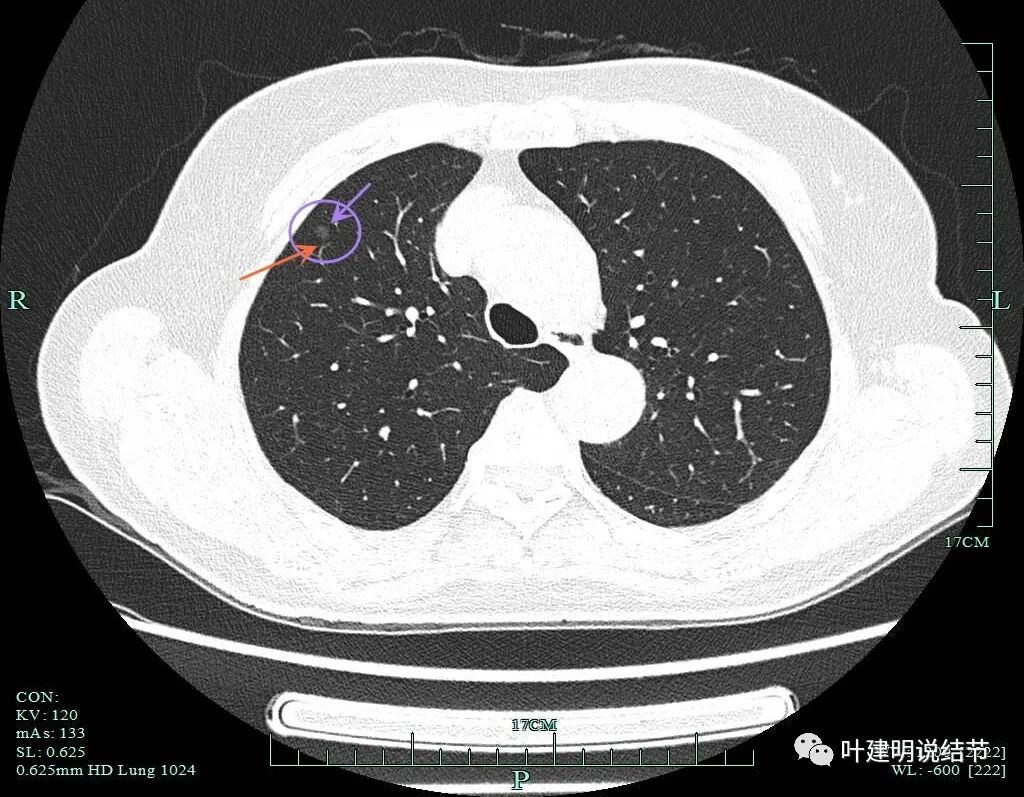

病灶8:右下叶磨玻璃结节了,轮廓清,血管贴边,边缘显毛糙。

有明显小血管进入,小血管有异常增粗。从密度考虑不典型增生可能性大,但因血管进入升一级考虑,原位癌可能性大点。如果没有上叶病灶6存在,此灶可随访,近期风险不算高。

病灶9:右中叶实性结节,密度过高,小而实的结节以良性可能性大。

病灶6重建后显示血管进入与穿行。

病灶2重建后显示瘤肺边界清以及血管进入。

病灶8重建后显示血管与结节间没有间隙,而且瘤肺边界很清。

病灶9的重建发现不是实性结节,而混合磨玻璃密度。绿色箭头示边上有磨玻璃成分,而且紫色箭头示边缘是毛糙的,红色箭头示整体轮廓是清的。

上图也显示病灶边缘毛糙,不光滑,与胶原结节、淋巴结等良性结节是不符合的。